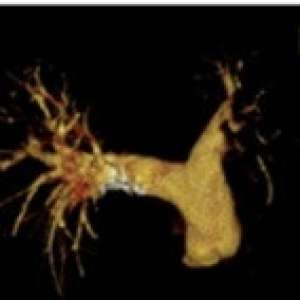

Инфекционная аневризма сосуда головного мозга

Мужчина, 70 лет

Родом из Новой Зеландии, направлен с проявлениями дисфазии и нехарактерного поведения.

Сопутствующие заболевания отрицает, ранее курил трубку, в настоящее время живет в отдаленной местности в доме на колесах.

В течение нескольких последних месяцев пациент неоднократно обращался к своему терапевту с жалобами на постоянную тошноту, усталость и потерю веса. Он был госпитализирован в терапевтическое отделение с диагнозом «кахексия» в связи с непреднамеренной потерей веса примерно на 20 кг за 2 месяца.

Лечащий врач, наблюдавший его во время первой госпитализации, отметил, что у него был слегка повышен уровень С-реактивного белка. Была выполнена КТ ОГК, ОБП и ОМТ, но признаков злокачественных новообразований или эмболии не было выявлено. Также выполнены ЭГДС и колоноскопия - отклонений не выявлено. Обращал на себя внимание новый комбинированный систолический и низкочастотный ранний диастолический шум над аортой. Пациент был выписан и рекомендовано проведение ЭХО-КГ в амбулаторных условиях.

В ожидании результатов амбулаторного обследования пациент пришёл в гости к своей сестре в состоянии спутанности сознания и с затруднённой речью. Сестра пациента вызвала скорую помощь.